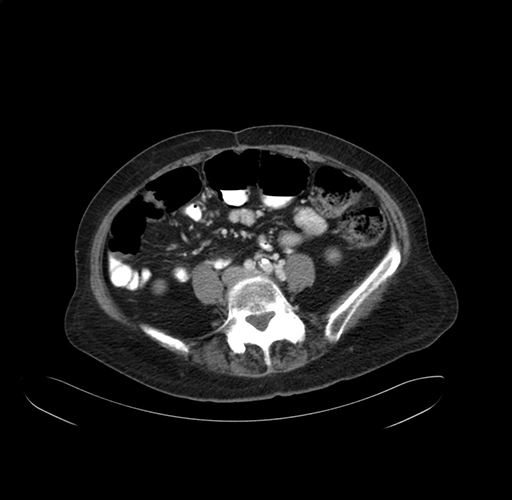

Pre-Chemo: Axial Venous

Axial Venous

Based on your CT findings, which issue(s) would give reason for "planned slowing down moment(s)" in this case?

Considering a standard right hepatectomy procedure, what step(s) of the operation would you do differently in this case?